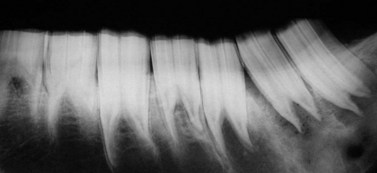

Fig. 8.10 Post mortem radiograph of a hemimandible with a caudal supernumerary CT. In addition, there are focal, lytic areas in the sclerotic mandibular bone under 311 associated with marked periodontal disease clinically evident around this tooth.

image